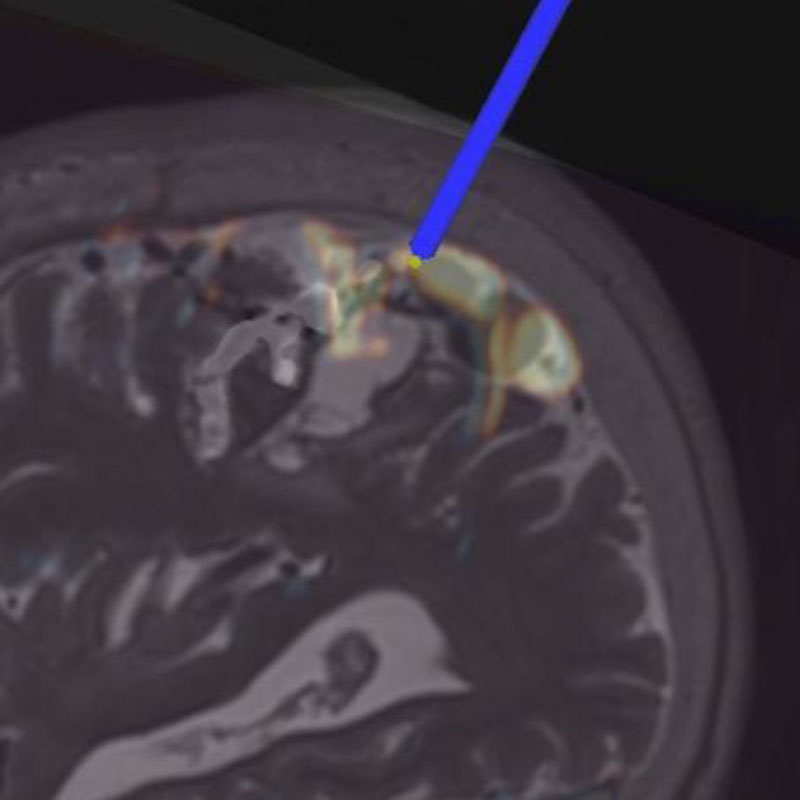

手術中

モニタリング